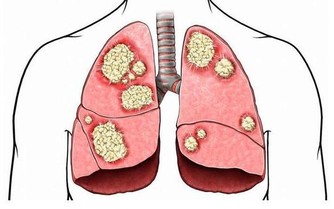

我們再來了解一下飲酒對肝臟方面的影響,肝細胞在乙醛的強烈刺激下會表現得非常興奮,也會合成更多包括甘油三酯、高密度脂蛋白等在內的脂肪,甘油三酯為大量積存在肝細胞當中,此時脂肪肝便發生了,長久以往會使肝細胞持續受到損傷。

過多的脂肪進入到血管之後,因乙醛損傷了血管內皮,而更容易沉積在血管的內皮之下,促進與加速了血管病變的發生。